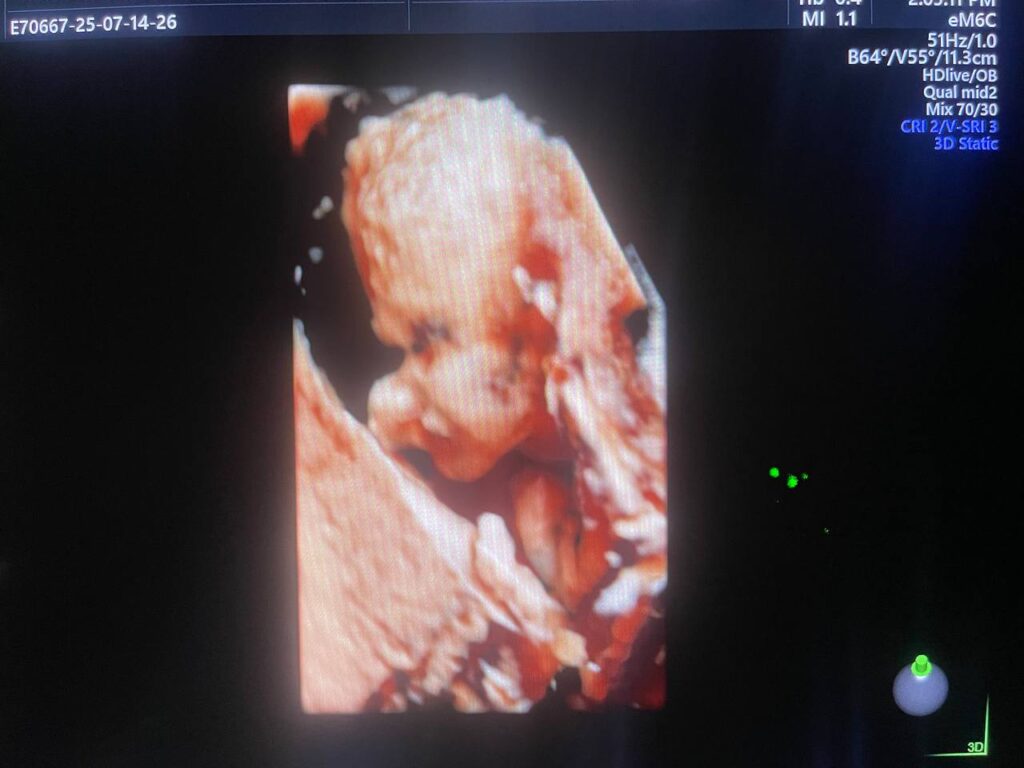

Multiple Craniofacial anomaly seen , mild dilated posterior atrium of the lateral ventricle 10.3mm , agenesis of the corpus callosum ??can not be excldued , bilateral cleft lip & palate , small orbits & hand anomaly , congenital heart disease can not be excldued , please for further study & echocardiography , Patau Syndrome? (Trisomy 13 ? ) can not be excldued ? please further study , no other anomaly can be detected now